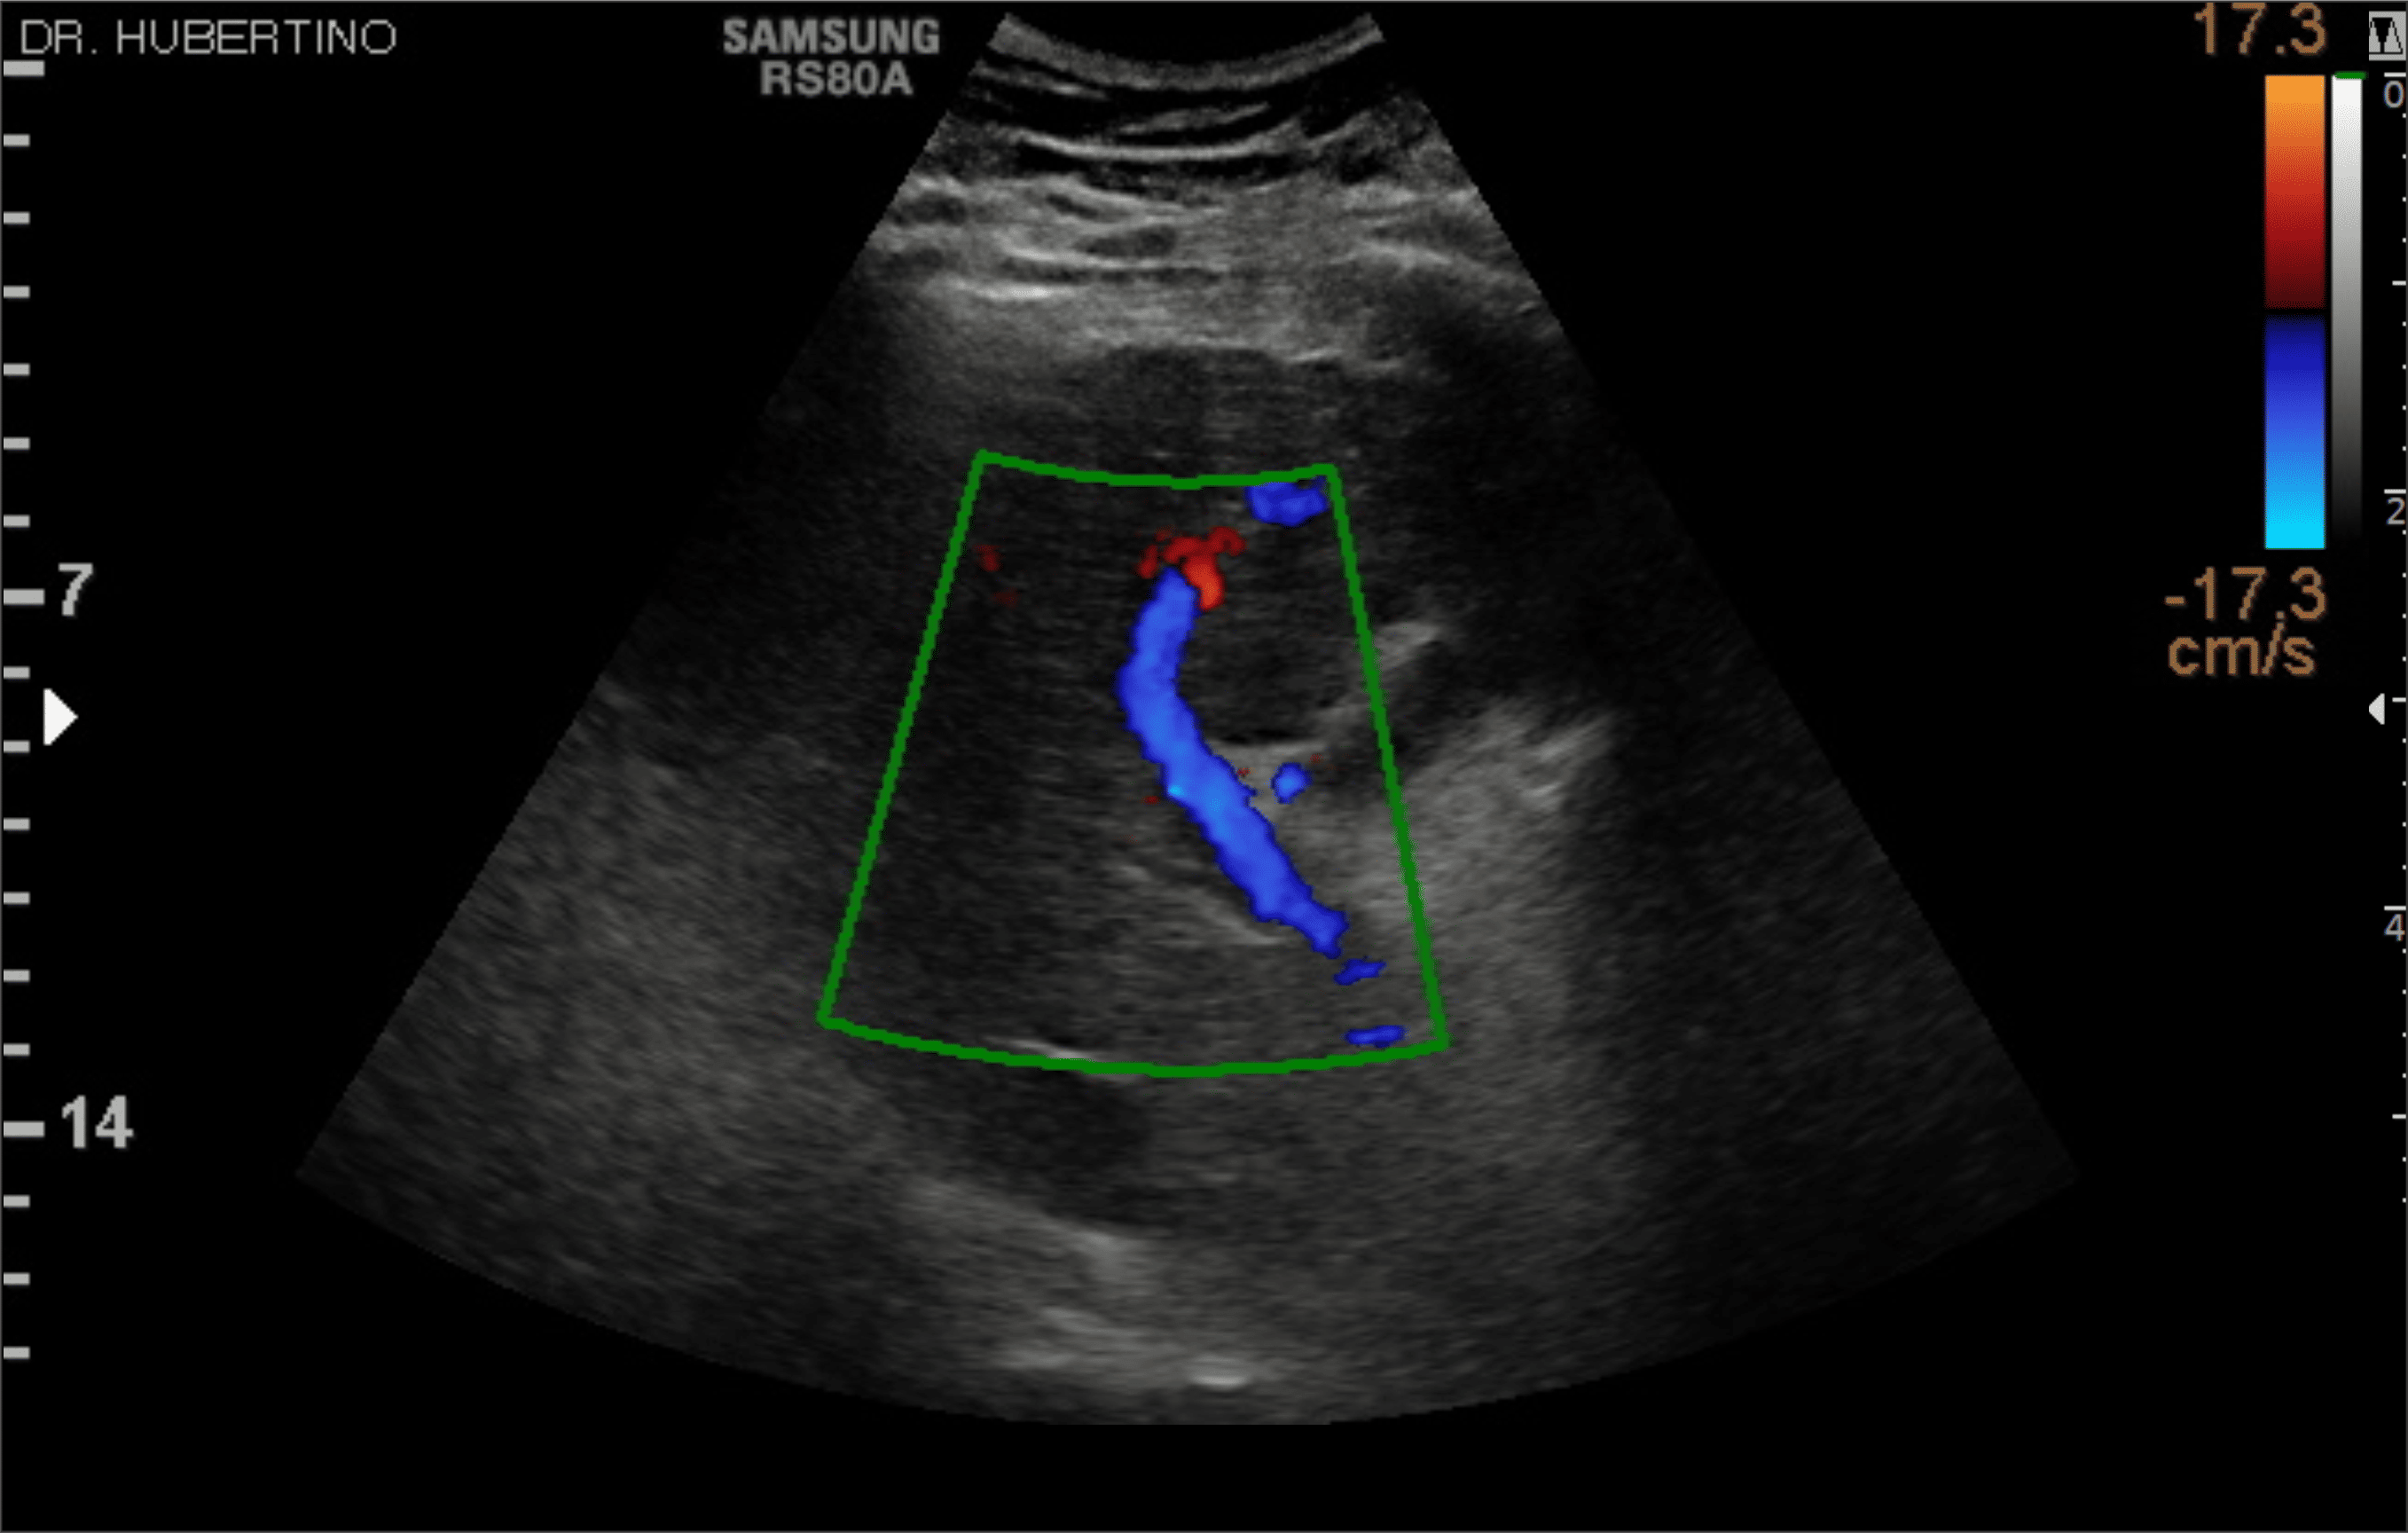

En Diagnoimagen incorporamos un enfoque de ecografía multiparamétrica, combinando modo B, Doppler color, Doppler de microflujo y elastografía, lo que nos permite una evaluación más completa y precisa en múltiples patologías.

🔹La ecografía Doppler permite evaluar el flujo sanguíneo en arterias y venas, siendo fundamental para el diagnóstico de insuficiencia venosa, várices, trombosis, estenosis carotídea y patología hepática.